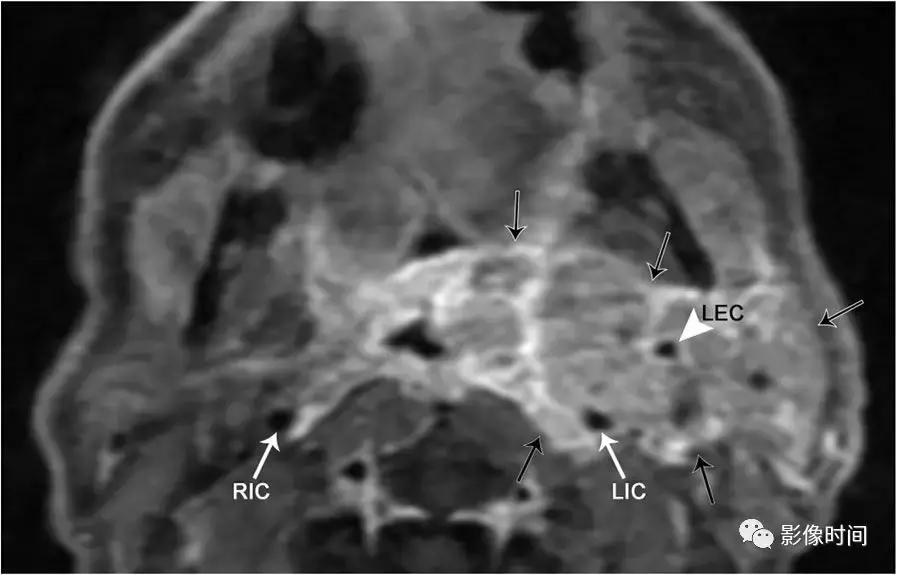

轴位 T1WI+C 显示不均匀强化肿块,完全包裹左侧颈内 (LIC) 和颈外动脉 (LEC)。注意左侧颈内动脉的管腔与右侧颈内动脉 (RIC) 的管径一致。